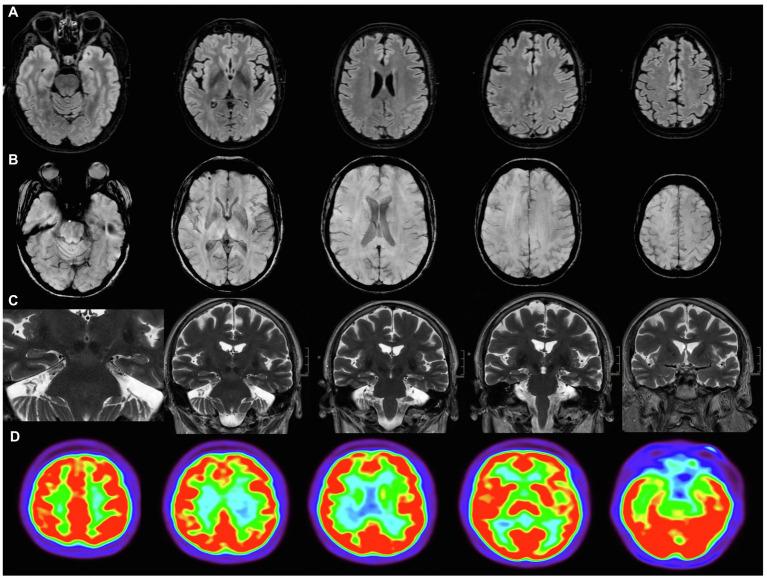

"Brain Fog" by COVID-19 or Alzheimer's Disease? A Case Report.

Cognitive symptoms after COVID-19 have been increasingly recognized several months after the acute infection and have been designated as "brain fog." We report a patient with cognitive symptoms that started immediately after COVID-19, in which cerebrospinal fluid biomarkers were highly suggestive of Alzheimer's disease. Our case highlights the need to examine patients with cognitive symptoms following COVID-19 comprehensively. A detailed assessment combining clinical, cognitive, and biomarker studies may help disentangle the underlying mechanisms associated with cognitive dysfunction in each case. The investigation of neurodegenerative processes in an early stage, especially in older patients, is probably warranted.